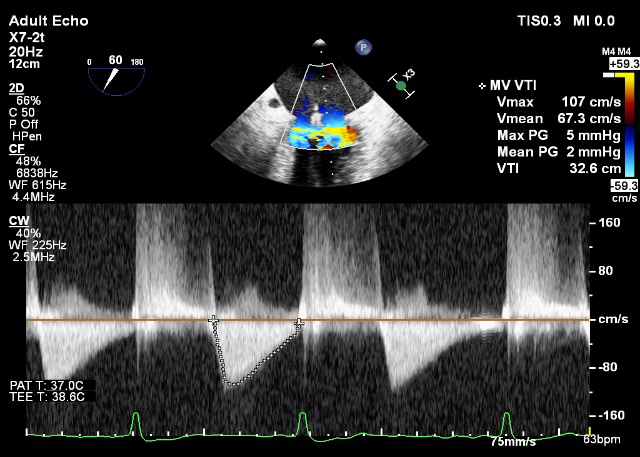

LVOT-color:MR(重度),返流面积11.3cm2

TEE LVOT切面返流量评估

TEE 4-Ch view返流量评估